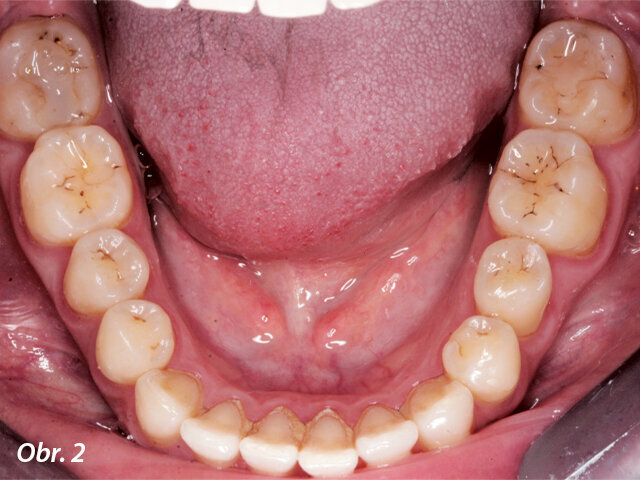

Kazuistika

Pacientka ve věku 38 let přišla do mé ordinace kvůli vyřešení zubních kazů. Při klinickém vyšetření nebyly patrné žádné kazy velkého rozsahu (obr. 1, 2). Až na RTG snímcích typu bitewing (obr. 3, 4), nezbytného prostředku pro diagnostiku v záchovné stomatologii, byly vidět mnohé kariézní léze, které zasahovaly do dentinových tkání. Pacientka požadovala vynikající estetický výsledek, což znamenalo sladění kompozitního materiálu se sklovinnými tkáněmi. Tento požadavek musel být zkombinován s funkční rehabilitací, která by v distálním úseku odolala zatížení žvýkacími silami a zajistila dlouhodobě minimální možné opotřebení. V rámci léčebného plánu bylo pacientce navrženo řešení v podobě přímého ošetření kazů v jednotlivých kvadrantech a nepřímé výplně v zubu 47, které by umožňovalo nejlepší přesnost okrajů a bylo zárukou dlouhodobě vynikajícího výsledku.